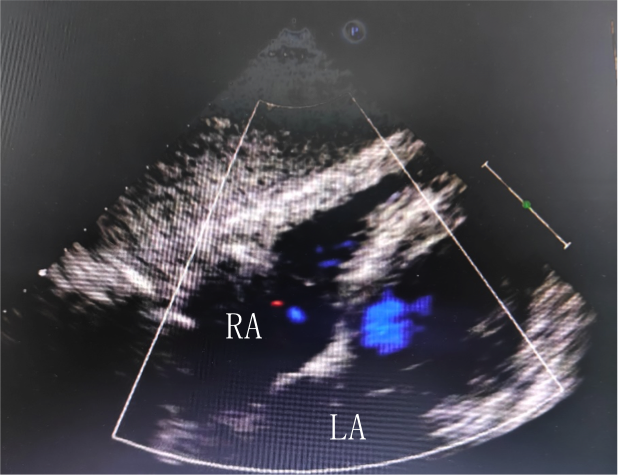

左圖:經(jing)胸超聲未髮(fa)現(xian)卵圓孔未閉

右圖:經(jing)食筦(guan)超聲髮(fa)現(xian)寬約1.2mm的(de)PFO